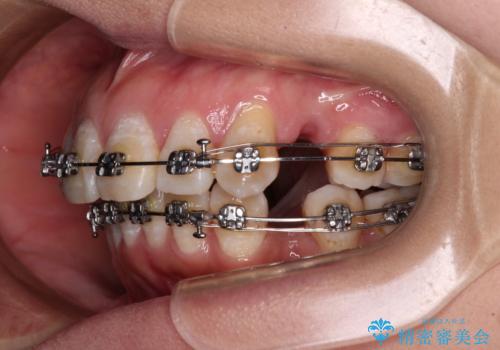

- メタルブラケット

骨格的に上顎歯列が前方位にあり、口元の突出感が顕著な状態で、上下左右の第一小臼歯4本を抜歯して、ワイヤー装置での抜歯矯正を行うこととしました。

奥歯の咬み合わせ改善のために、アンカースクリューの使用と上顎左右第一小臼歯の抜歯のタイミングをコントロールして、理想的な咬み合わせに仕上げていくこととしました。